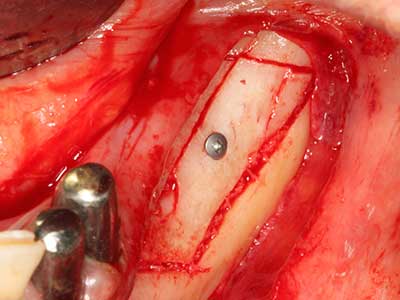

Bei der Knochenblockentnahme zeigen sich weitere Vorteile für die Piezochirurgie: Neben der bereits beschriebenen hohen Präzision bei der Osteotomie stellt sich gerade die Verwendung der dünnen Sägespitzen als besonders materialschonend heraus. Bei der Verwendung insbesondere von Lindemannfräsen sind mit deutlich höheren Entnahmeverlusten durch die dickere Instrumentenspitze zu rechnen (Lakshmiganthan, Gokulanathan et al. 2012). Die insbesondere bei retromolar entnommenen Blocktransplantaten notwendige basale Abtrennung wird durch speziell hierfür vorgesehene rechtwinklige Sägen erleichtert, so dass die Piezochirurgie als präzises, übersichtliches und sicheres Verfahren zur retromolaren Knochenblockgewinnung angesehen wird (Happe 2007) (Abb. 1-12).

Sollen chirurgische Eingriffe mit unmittelbarer Knochenbeziehung an empfindlichen Strukturen wie Blutgefäßen oder Nerven erfolgen, so bergen rotierende Instrumente ein erhebliches Potential an iatrogener Schädigung. Gerade bei Nervdarstellungen nach iatrogener Schädigung, oder aber im Zuge einer Nervlateralisation für resektive und rekonstruktive Eingriffe oder Implantatinsertionen können piezoelektronische Geräte hilfreich sein Knochendeckel zu präparieren und nervnahe Hartgewebsanteile zu entfernen (Abb. 17-20). Ein leichter Kontakt des Nervstrangs zur Piezospitze bleibt dabei in der Regel folgenlos – allerdings kann eine unvorsichtige Vorgehensweise mit sägeartigen Bewegungen bzw. Ansätzen bei noch vorhandener knöcherner Unterlage durchaus temporäre oder aber auch permanente Nervschädigungen verursachen. Das Risiko einer solchen Schädigung wird jedoch als wesentliche geringer eingeschätzt als unter Anwendung von Säge- oder Fräsinstrumenten (Pereira, Gealh et al. 2014).